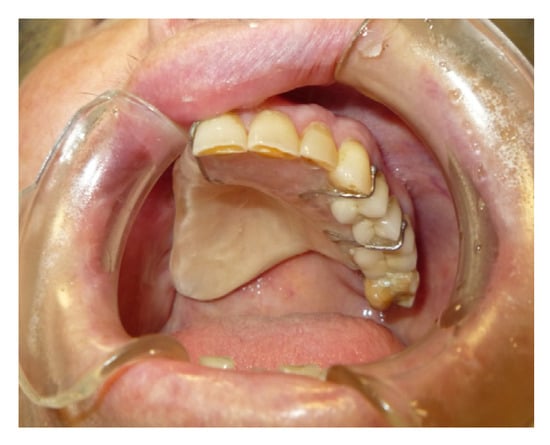

3.1.3. Case 3: R.M.

| R.M. | X | * | 9 | 0 | ||